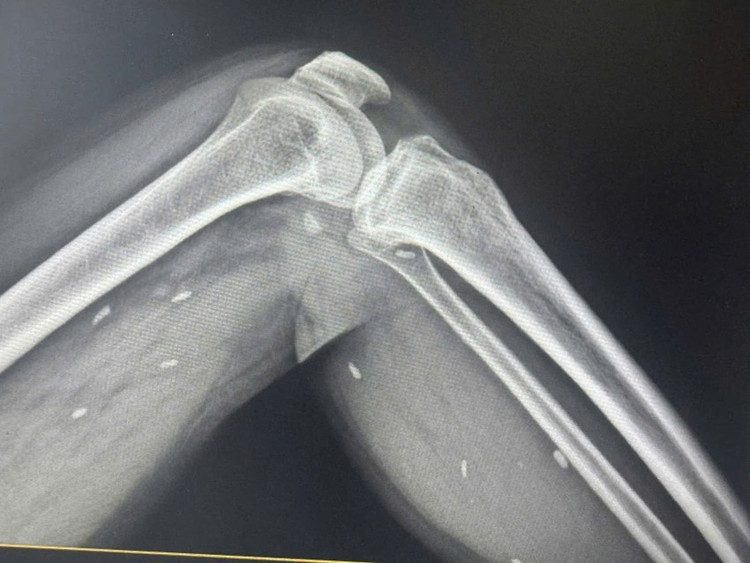

Nhiều kén sán nằm trong mô vùng xương đùi và cẳng chân bệnh nhân/Ảnh plo.vn

Kết quả cho thấy nhiều kén sán có kích thước tương đương hạt gạo, nằm rải rác trong các mô mềm vùng xương đùi và cẳng chân. Bác sĩ nhận định đây là hình ảnh điển hình của tình trạng nhiễm kén sán.

Người bệnh T.T.H đến Trung tâm y tế để thăm khám sau khi có dấu hiệu mệt mỏi, đau nhức nhiều ở vùng chân, lưng và vận động khó khăn. Bác sĩ đã chỉ định chụp X- quang để kiểm tra.